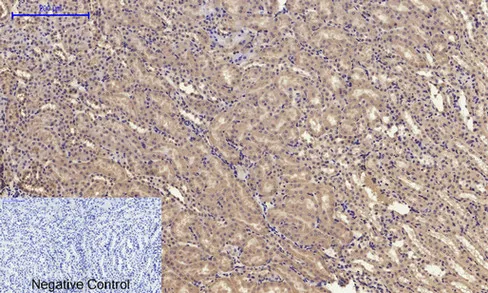

Glut4 Rabbit Polyclonal Antibody

Cat: APRab11504